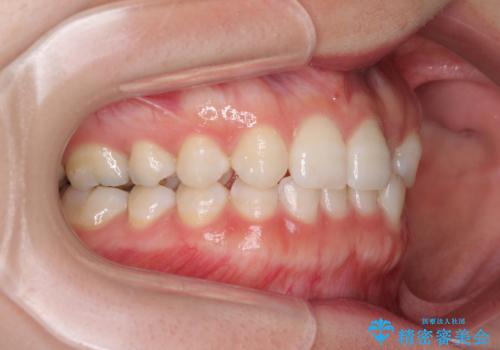

海外転居前に気になる前歯を整えたい 上下前歯の部分矯正

- 1年後に海外に転居するため、気になる前歯を矯正治療で整えたいとのことで来院された患者様です。

下顎は叢生が強かったため、奥歯までワイヤーを装着し、上顎は前歯の一部のみ気になっていたので、その部分にだけワイヤー装置を装着することとしました。